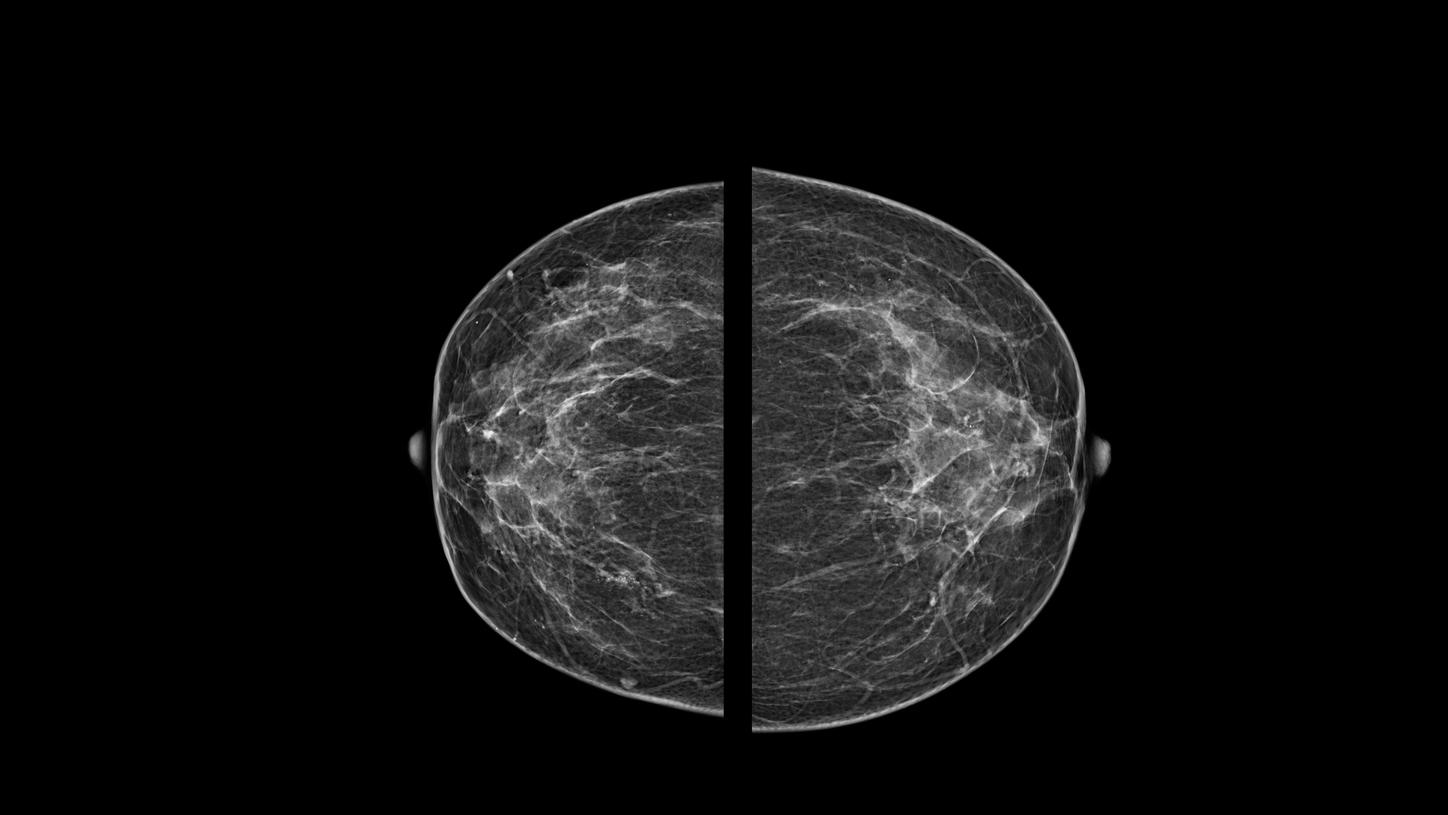

Paciente assintomática de 48 anos, realizou mamografia de rastreio (imagem 1 e 2) que evidenciou um pequeno grupamento de microcalcificações com morfologia pleomórfica e distribuição segmentar, localizado na UQM (união dos quadrantes mediais) da mama direita, não disponibilizou exames anteriores e retornou ao mastologista que solicitou core-biópsia por estereotataxia.